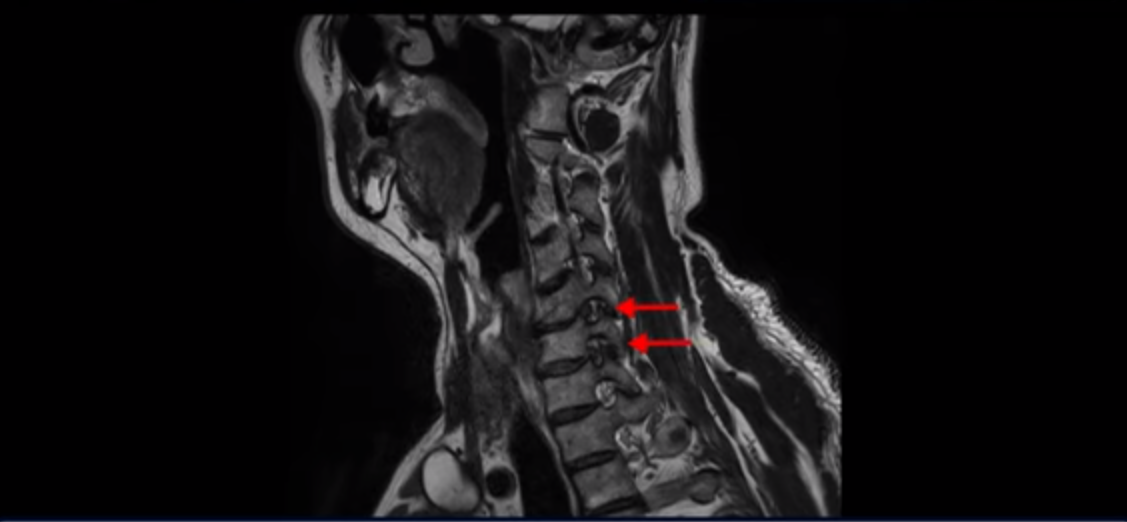

우선 이분 증상은 좌측 어깨와 팔 통증입니다. 이분 MRI를 보면 5번 6번과 6번 7번이 안 좋아 보입니다.

5번 6번에는 오른쪽과 왼쪽 모두 디스크 파열이 있고,

6번 7번에는 왼쪽으로 디스크가 밀려 나와 있습니다.

왼쪽으로 신경이 빠져나가는 추간공을 보면 보시다시피 5번 6번과 6번 7번 신경 구멍이 아래나 위에 비해 막혀있는 게 보입니다.

디스크도 밀려 나와 있고 협착도 있는 겁니다.

이분 왼쪽 어깨와 팔 통증이 갑자기 생긴 이유는 5번 6번 디스크 또는 6번 7번 디스크가 갑자기 밀려 나온 것이 원인일 것으로 보이는데, 그럼 이 디스크들이 밀려 나와서 신경을 자극하거나 누르는데 어떻게 이게 수술 없이도 좋아질 수 있는 걸까요?